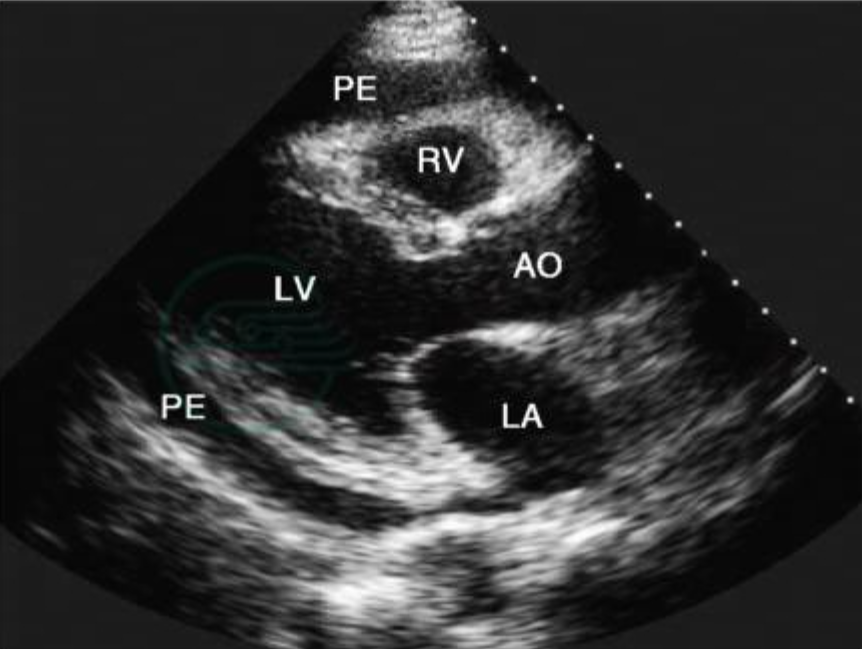

图片信息来源:胸骨旁长轴切面(PLAX)示心包积液

这是心包积液在超声上的基础表现。当液体在心包腔内聚集时,在二维超声图像中通常表现为无回声或低回声区域(Echo-free space),位于:脏层心包(Visceral pericardium)与壁层心包(Parietal pericardium)之间。

在少量积液时,这种无回声区往往首先出现在左心室后方,随着液体逐渐增多,液性暗区可能会向心脏周围扩展,甚至形成环绕心脏的表现。

在ARDMS考试题目中,题干经常会通过类似描述来提示考生,例如:"Echo-free space surrounding the heart"或"Echo-free space posterior to the LV",这些表述往往是在提示Pericardial Effusion(心包积液)的存在。

通常只在左心室后方可以观察到一条较窄的无回声区(Echo-free space)。其特点包括:多见于Posterior LV wall(左室后壁);未形成环绕心脏的液体分布;宽度通常<10mm。如果题干描述仅在LV posterior区域出现echo-free space,往往就是在提示small pericardial effusion。